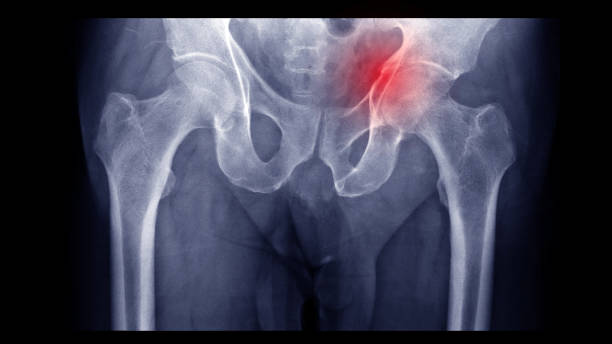

Acetabulum Fracture Surgery